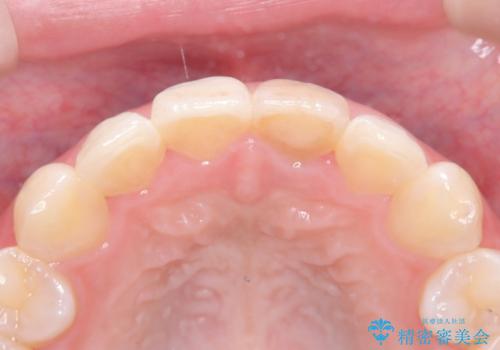

土台(ファイバーコア)の構築: 金属の土台は将来的な変色の原因となるため、光の透過性が高く、歯のしなりに近い性質を持つファイバーコアを採用。これにより、被せ物の透明感を損なわず、歯の破折も防ぎます。

オールセラミッククラウンによる修復: 最終的な被せ物には、一切の金属を使用しないオールセラミックを選択。隣の天然歯と色調や透明感を精密に合わせることで、どこを治療したかわからないほど自然な仕上がりとなりました。